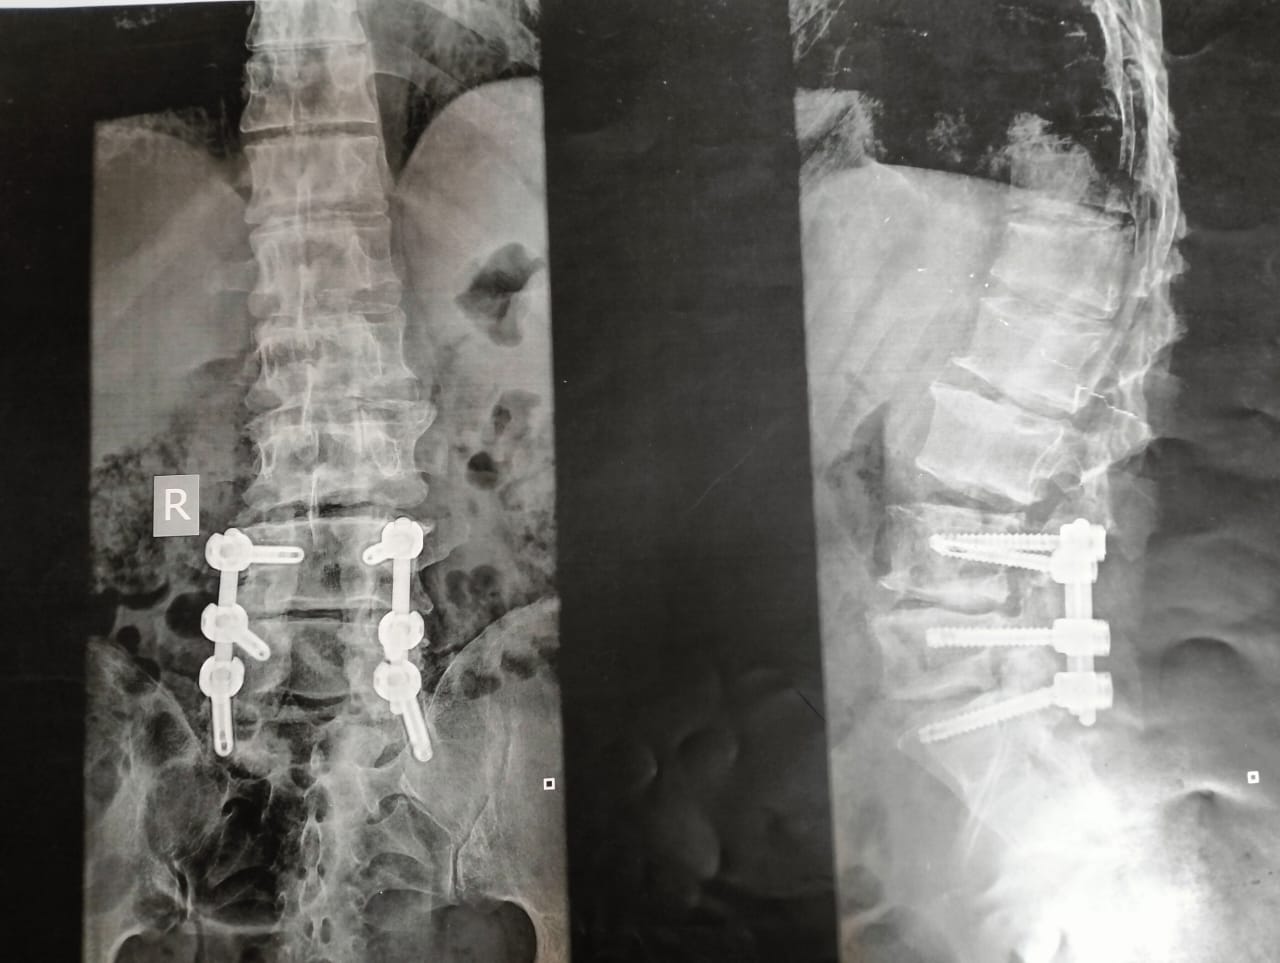

صورة أشعة للمسن توضح الاصابات الناتجة بسبب الاعتداء